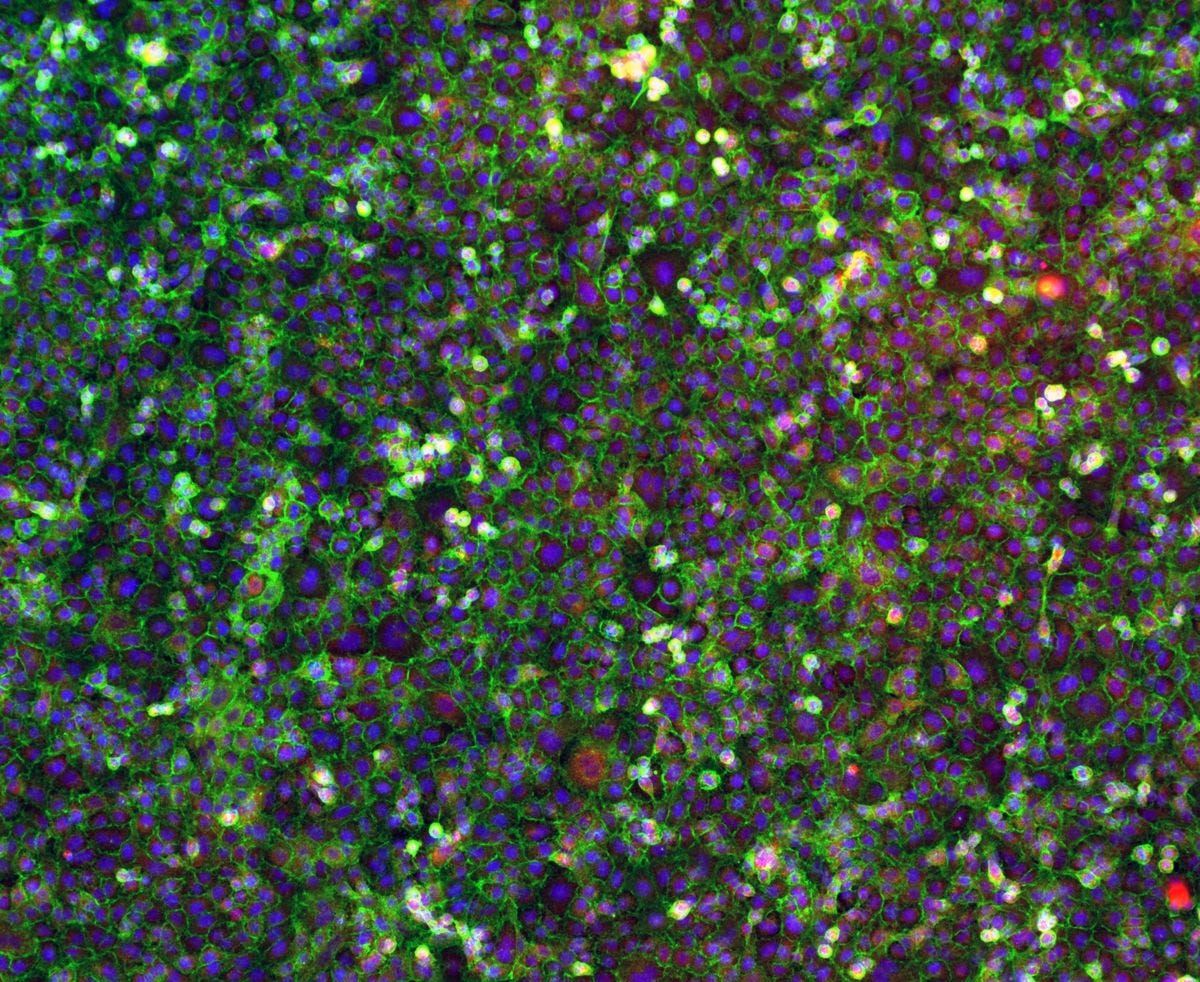

The toxicity of nanoparticles (nanotoxicity) depends on size, shape, chemical composition, and surface properties. Smaller particles are more reactive and penetrate tissues more easily. Rod-shaped or plate-shaped particles can physically disturb cell surfaces. Surface chemistry can make nanoparticles bind to proteins and trick the immune system into attacking normal tissues. These effects accumulate over time because synthetic nanoparticles are persistent. They do not degrade naturally and the body cannot fully eliminate them.

Exposure to nanoparticles had been previously associated with a range of acute and chronic effects. These range from inflammation, exacerbation of asthma, and metal fume fever to fibrosis, chronic inflammatory lung diseases, and carcinogenesis, as reported by the National Institutes of Health. Various studies have demonstrated that inhaled or ingested nanoparticles could enter systemic circulation and migrate to different organs and tissues.

Toxicities that happen at the cellular level are unique, according to Sayes. If a cell understands that it’s going through a substantial amount of damage, it has this control mechanism called apoptosis, which simply means cellular suicide. The cell might recognize it’s undergoing some toxic event and may choose to eliminate itself before that toxicity might spread to other surrounding cells into organs, organ systems, or the entire body. It’s a defense mechanism that animals and plants have against a contamination. So what happens at the cellular level sometimes may not extrapolate out to the entire organism level.

Sayes said most of the time when a toxicologist, or an environmental health specialist talks about nanotoxicology or nanotoxicity, they are referring to adverse health effects that happens at the cellular level. That’s because a nanomaterial is so small, that the very first interaction that a nanomaterial might have after exposure occurs at the cellular level.

Nanoparticles have been shown time and time again to penetrate and permeate through cell membranes, but it’s also able, because of its small size, to travel in our airways, in the lungs to areas that larger particles usually cannot reach. In fact, some studies have shown that nanoparticles can translocate from the lung to the circulatory system.